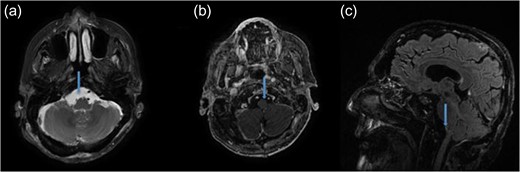

The patient underwent microsurgical resection via far-lateral transcondylar approach in park bench position (Fig. 2a). The tumor was tan-colored and extremely firm, extending inferiorly to the entrance of the vertebral artery. It also extended into the hypoglossal canal and jugular foramen (Fig. 2b). The PICA, which was initially encased by tumor, and cranial nerve IX, X and XI were all preserved (Fig. 2c). Gross total resection was achieved (Fig. 2d). No changes of motor evoked potentials were observed throughout the surgery. The postoperative course was uneventful and images confirmed gross total resection (Fig. 3, video 1). Histopathological examination of the tumor revealed prostate adenocarcinoma metastasis positive for prostatic specific antigen. There was focal necrosis and a high proliferative index assessed by Ki 67.

Postoperative MRI demonstrating the gross total mass resection. (a) Axial T2-weighted MRI. (b) Axial T1-weighted contrast enhanced MRI. (c) Sagittal T1-weighted contrast enhanced MRI.